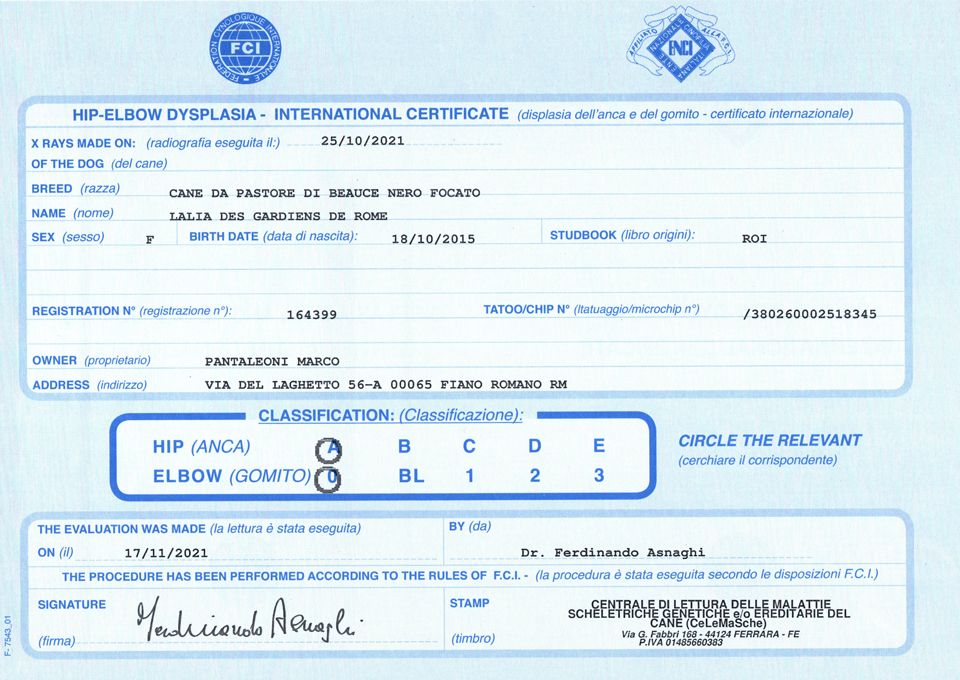

Lalia Des Gardiens De Rome

femelle

Berger de Beauce

18/10/2015

| Puce | 380260002518345 |

| Inscrit au LOF ? | Italie |

| N° origine | LOI 164399 |